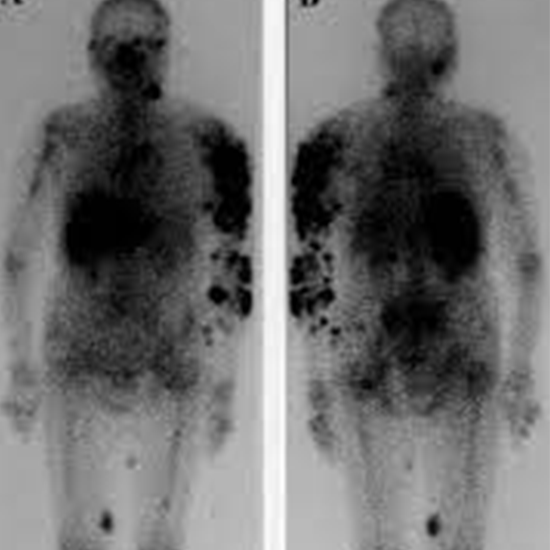

gallium whole body scan

Gallium whole body scan is a type of nuclear medicine scan. It is performed looking for infection, inflammation, and tumours in the body. To conduct a scan, a radioactive metal “Gallium”, is mixed into a solution and injected into your arm.

The solution moves through the blood and collects in organs and bones. The body will be scanned after giving an injection to see where and how the gallium accumulated in your body.